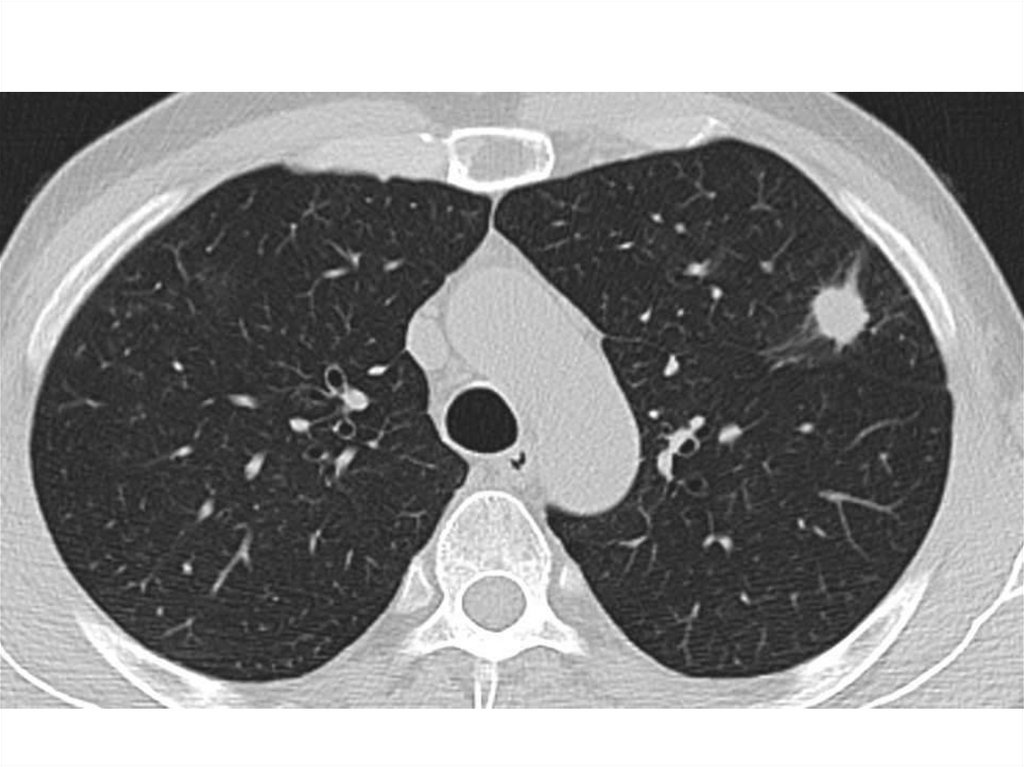

Компьютерная томография